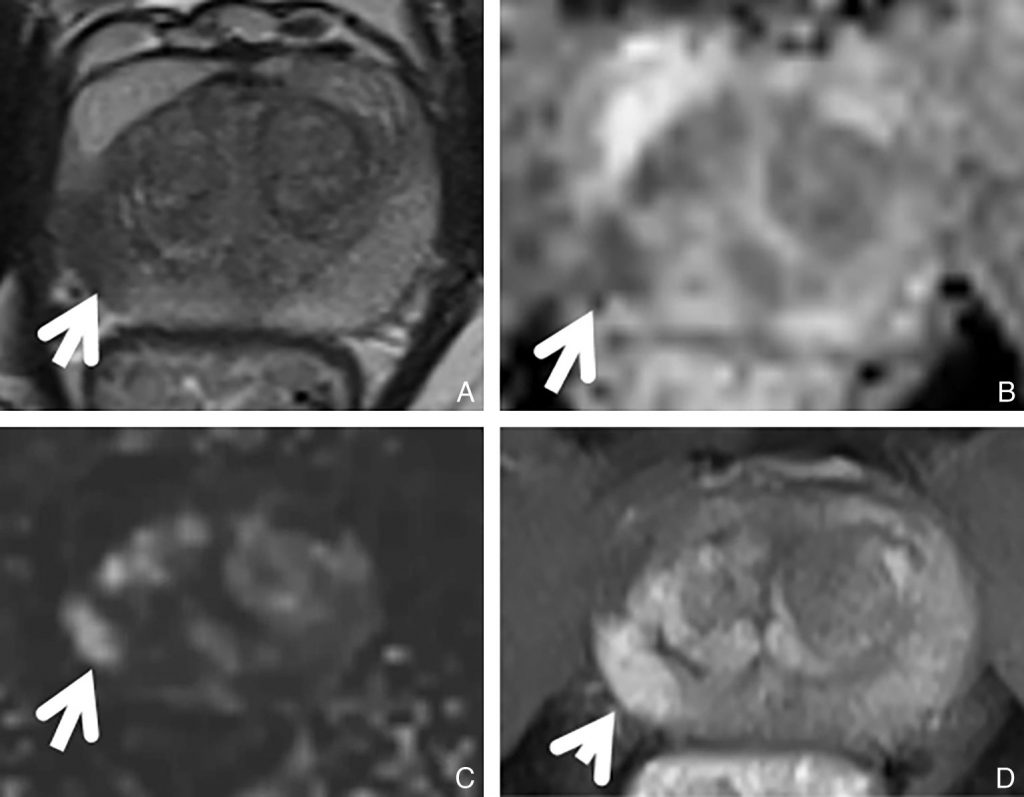

En IRM (figure 30.2), le cancer de la prostate apparaît :

- en hyposignal sur la séquence T2 ;

- en restriction de diffusion (comme la plupart des cancers) en hyposignal sur la carte ADC (la carte du coefficient apparent de diffusion) et en hypersignal sur la séquence de diffusion ;

- hypervascularisé, se rehaussant précocement par rapport au reste de la zone périphérique prostatique sur la séquence T1 avec injection.

Fig. 30.2 IRM prostatique d’un adénocarcinome prostatique Gleason 7 du lobe droit.

Le cancer de la prostate (flèche) apparaît en hyposignal sur la séquence T2 (A). Il présente une restriction de diffusion visible en hyposignal sur la carte du coefficient apparent de diffusion (B), en hypersignal sur la séquence de diffusion, (C) et se rehaussant précocement par rapport au reste de la zone périphérique prostatique sur la séquence T1 avec injection de gadolinium (D).

Source : CERF, CNEBMN, 2022.